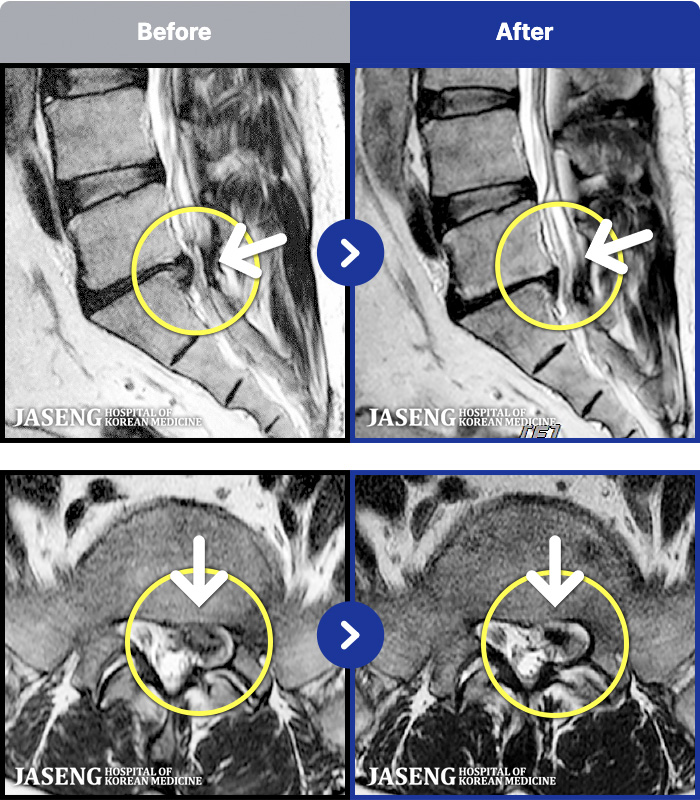

ȯںп Ǹ ǿ ԿǾ, ο ġ ۿ Ƿ ġḦ Ͻñ ٶϴ.